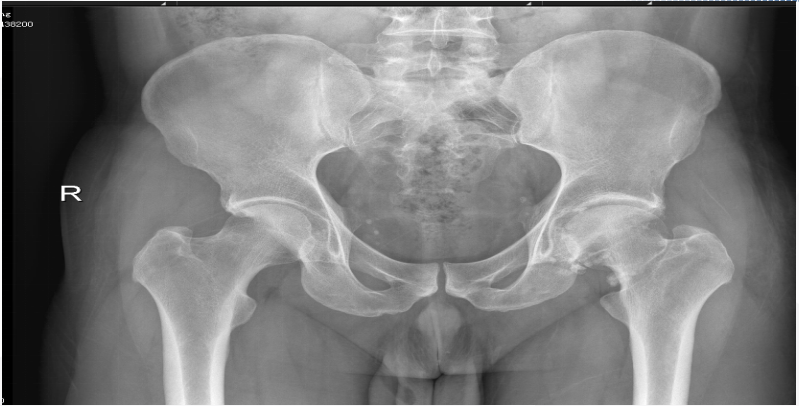

手术后髋关节情况

据了解,许叔叔是一位42岁左髋关节滑膜骨软骨瘤的患者,因反复左髋部疼痛10余年,加重3月余,服用6个月止痛药后症状无缓解,随即在家人的陪同下来到我院脊柱关节骨病外科就诊。脊柱关节骨病外科吴毅华副主任医师根据患者体格检查和影像学检查,诊断为:左髋关节滑膜骨软骨瘤,左髋骨性关节炎。吴毅华副主任医师介绍,髋关节为人体主要负重关节,周围软组织丰富,部位较深、关节腔狭小、周围有重要的血管神经,既往被视为关节镜的“禁区”。针对此类症状,通常的止痛药、理疗等保守治疗效果不理想,而传统切开关节探查手术则因为创伤大、损坏关节正常结构、术后康复缓慢等缺点,令人望而生畏。